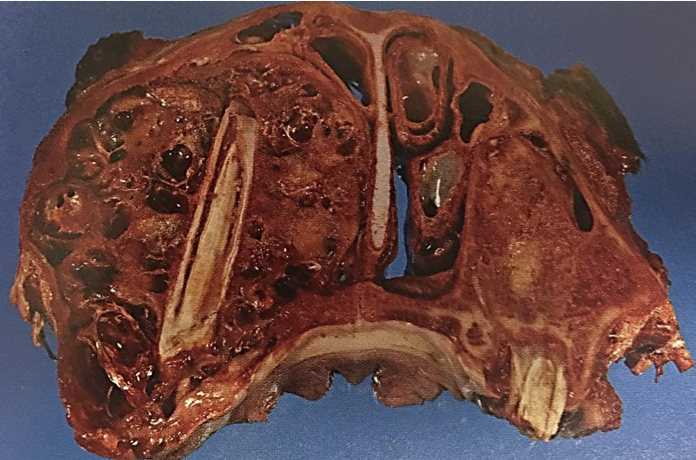

Ethmoid Hematoma